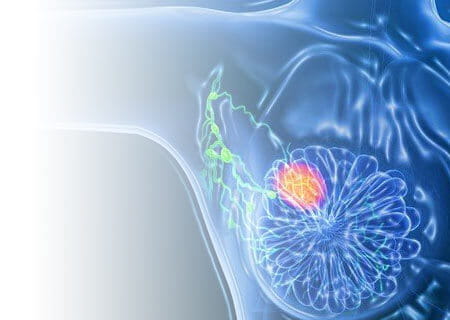

New Option for Recurrent Breast Cancer

Our team led a prospective study to demonstrate that women may be able to avoid mastectomy for recurrent breast cancer and instead use a far less morbid radiotherapy treatment with partial breast IORT. Read Study Results